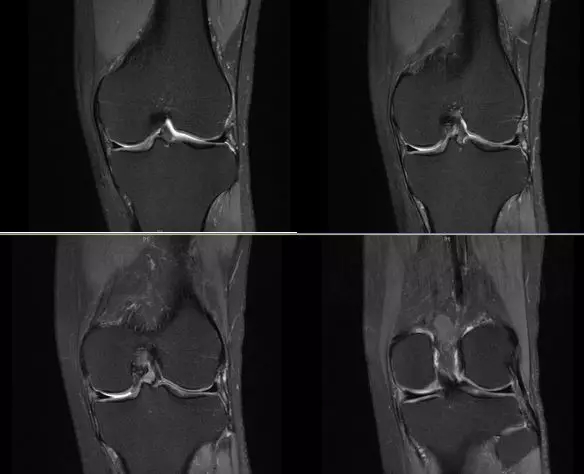

膝关节内侧副韧带

膝关节后外侧结构

内侧支持带撕裂

正常的膝关节

韧带结构:形态,张力,质地,连续性

半月板:完整性,形态,质地